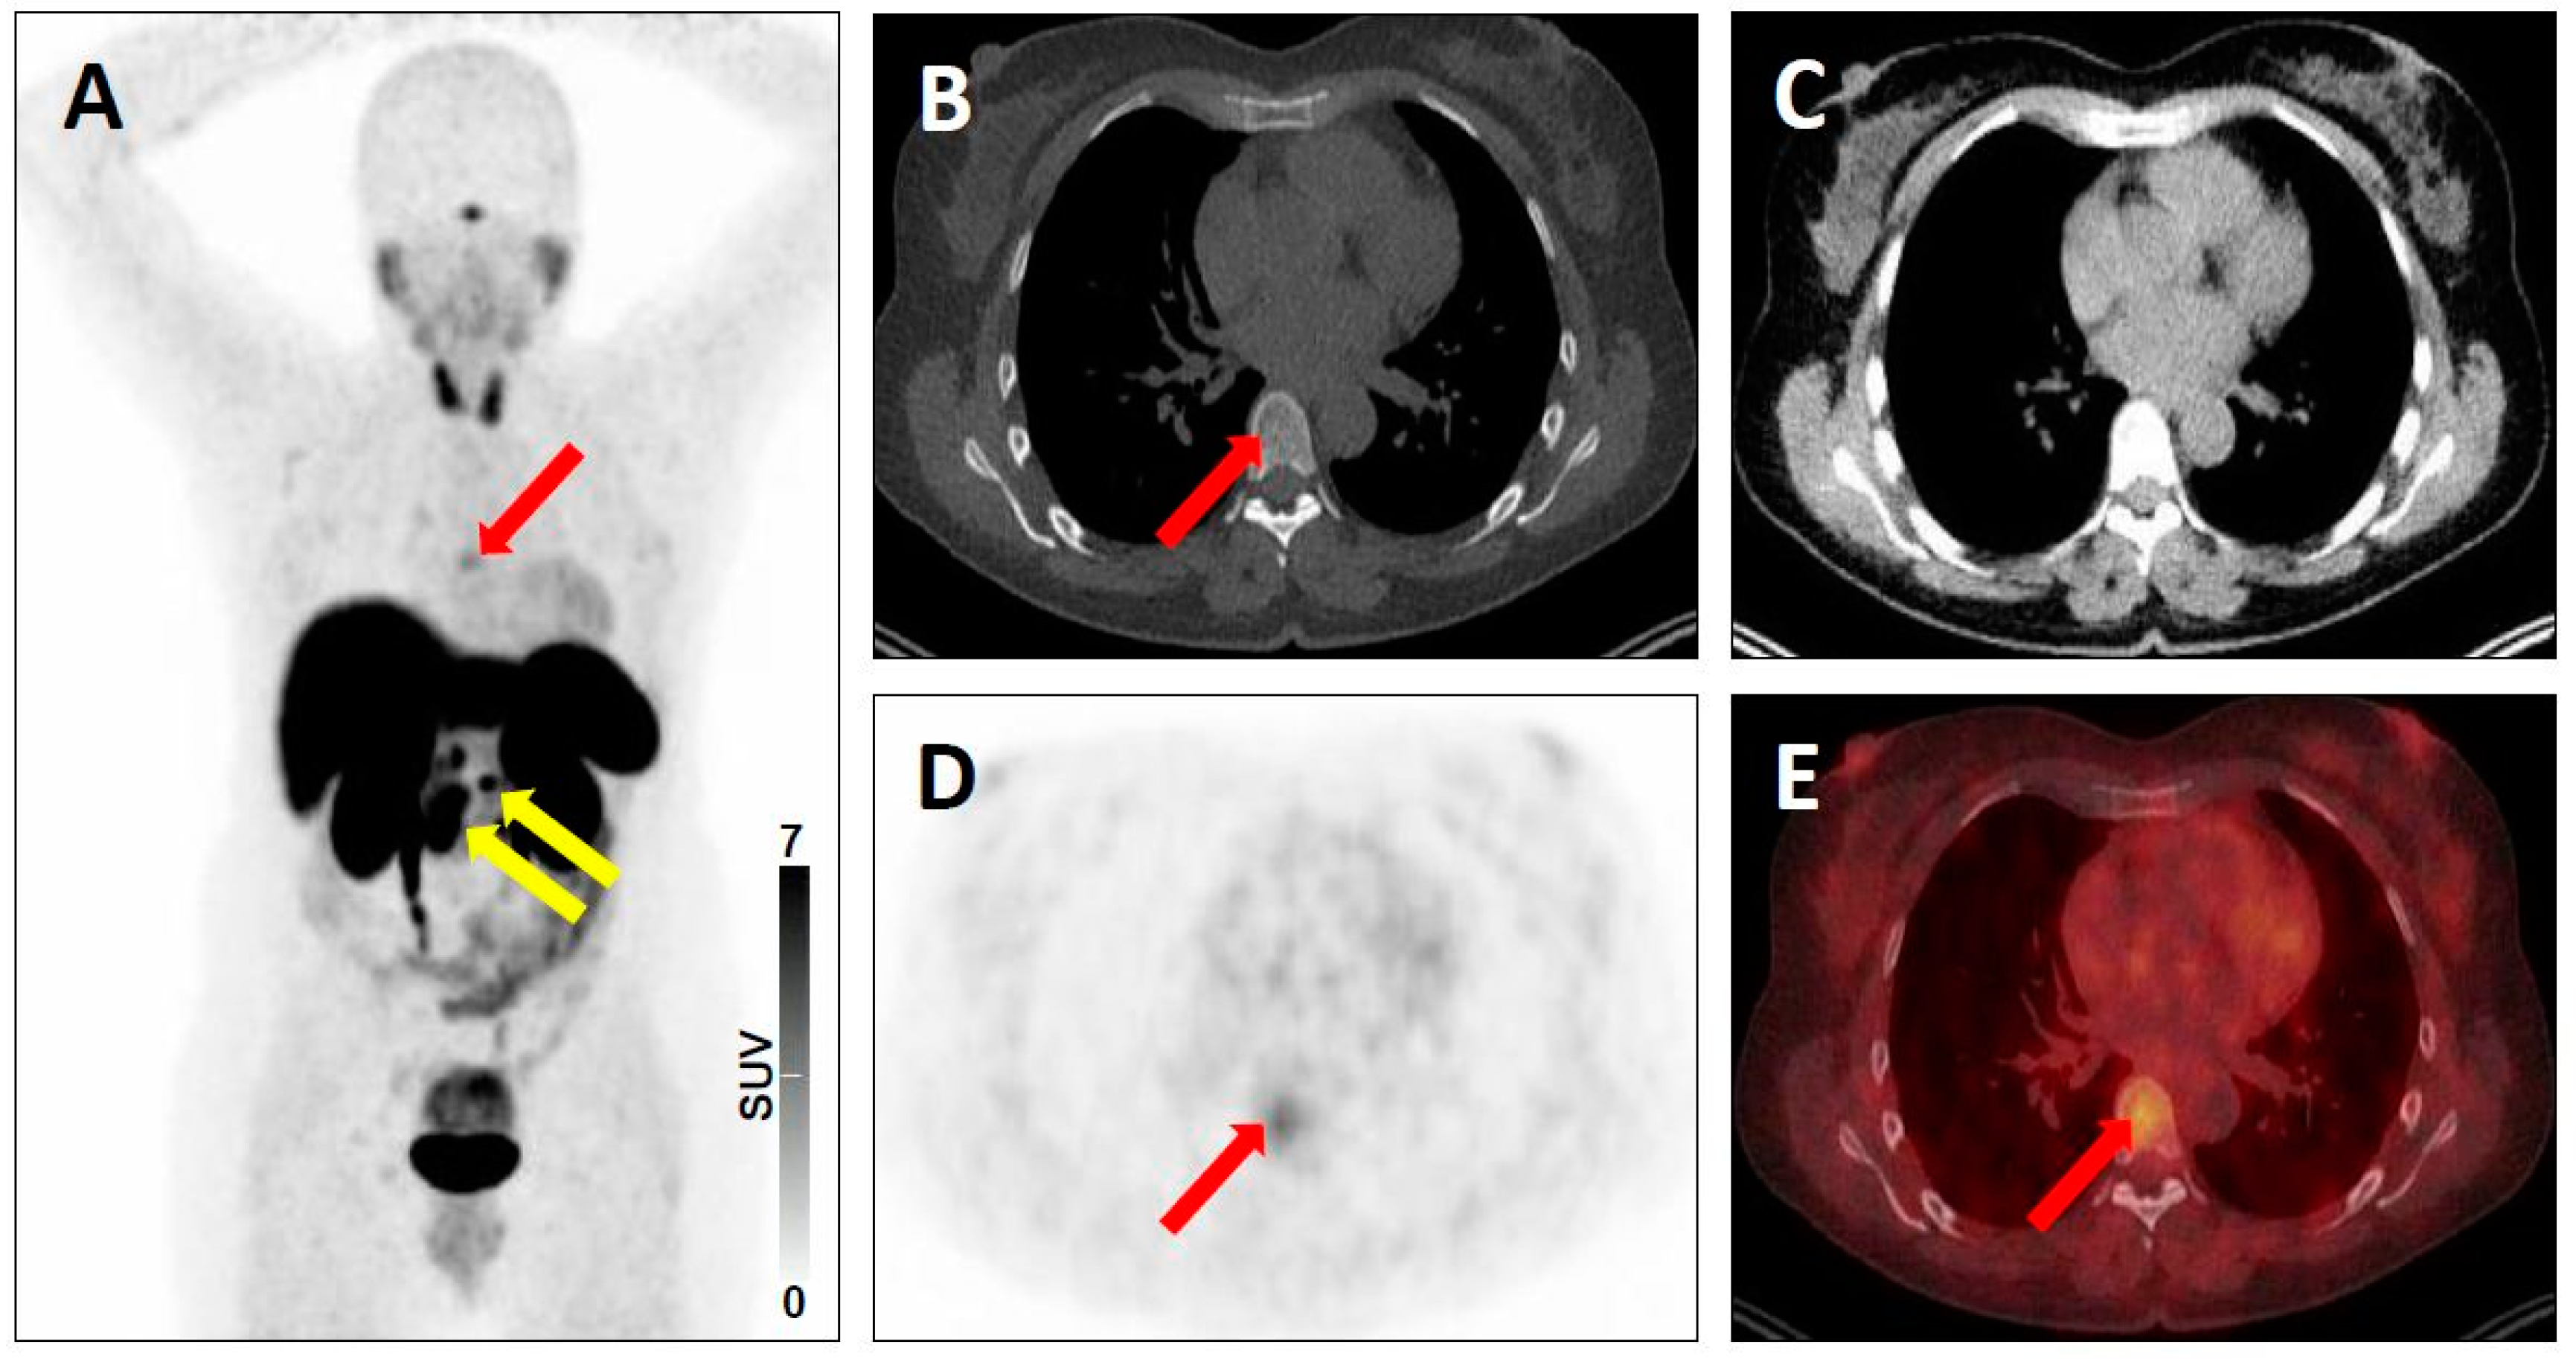

| 3 | 3A | - Regional lymph nodes, e.g. low-level uptake in mesenteric lymph node in midabdomen [20] - Mild radiotracer uptake in a supraclavicular lymph node [5] | - Pelvic lymph node involvement with low-level uptake [19] |

| 4 | - Intense uptake in a liver lesion without definitive findings on conventional imaging [20] | - Intense radiotracer uptake in a lymph node without definitive findings on conventional imaging [19] | |